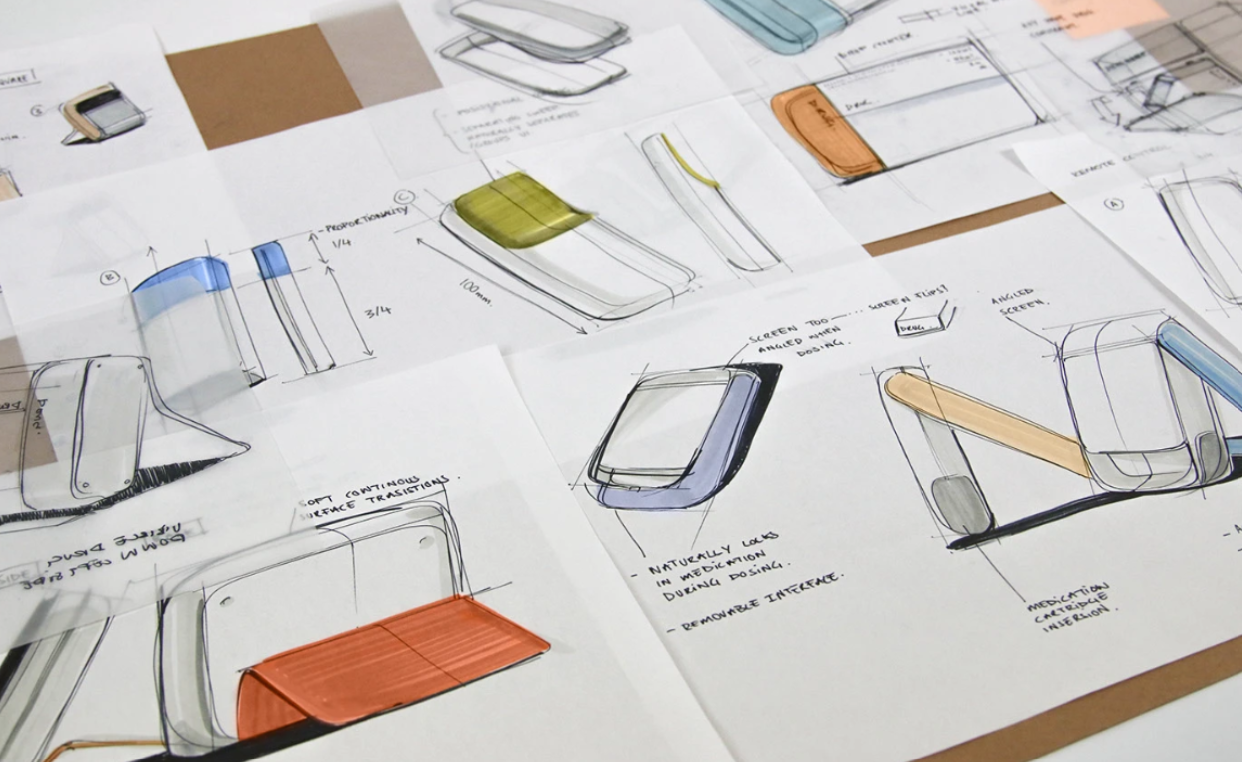

Ballad is a smart insulin pen that helps visually impaired diabetics self-administer insulin confidently. High-contrast touchpoints, a connected app with an enlarged dose display, and replaceable cartridges simplify treatment and promote independence while reducing plastic waste. (Cambridge Consultants)

Bamboo is a reusable autoinjector that improves usability while reducing environmental impact. With fewer parts, optimized design, and innovative drive systems, it saves space, energy, and costs, addressing the medical industry’s sustainability challenges. (Cambridge Consultants)

Falcon streamlines Parkinson’s treatment by replacing up to 120 monthly injections with a single implant refill. Designed for patients with reduced dexterity, it automates the refill process and provides clear, guided feedback to ensure safe and independent use. (Cambridge Consultants)

Ambulatory infusion pumps are notoriously complicated devices even for medical professionals. The FDA reported 710 deaths over a 5 year period linking many of which to human error. Robin provides automated workflows, intuitive feedback and reassurance for lay users and caregivers whilst maintaining flexibility and custom control for healthcare professionals.